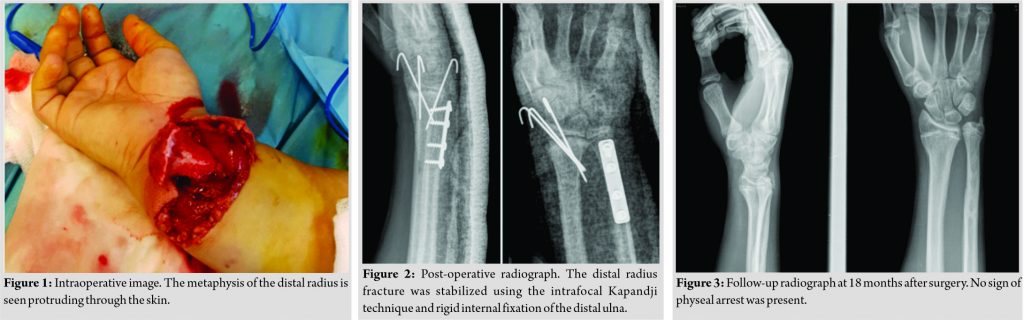

The first step in the surgery was making of an extension longitudinal incision of 2 cm in the middle of the volar side of the wrist, after which the metaphysis of the radius was manually relocated (Fig. 1). The wound and the bone fragments were irrigated with 5 L of isotonic sodium chloride solution. Attention was taken to recognize all the important structures of the volar site of the wrist. The median and ulnar nerves, the radial and ulnar arteries, such as the flexor tendons, were found to be intact. The metaphysis was then manually reduced to its normal position and fixed with three percutaneous Kirschner wires (Fig. 2). Great care has been taken not to pass the K-wires through the growth plate so that it does not affect its healing. A standard ulnar approach was used and a 5 cm incision was made over the fracture site. Standard dissection principles were applied to expose the ulnar fracture. After adequate reduction, a four-hole plate was placed over the fracture line and stabilized with 3.5mm cortical screws. The incisions were irrigated with normal saline and the wounds were closed in a normal layered fashion. Sterile dressings and a below-elbow cast were applied to the right upper limb.

Postoperatively, the patient was followed up in the outpatient clinic for 6 weeks, with once-weekly changing of the dressing and X-ray. After removal of the K-wires and cast at the end of the 6-week period, the patient was recommended a routine of gentle range of motion exercises. The patient attended additional follow-up at 6 months, 1 year, and 18 months. He achieved full range of motion and full strength of the wrist, with no radiographic signs of physeal arrest (Fig. 3 and 4). After 12 months, the patient scheduled surgery for material removal.

Open fractures in children are uncommon and usually the result of a high-energy trauma. Open distal radius fractures are even more uncommon. In our clinic, we managed an open fracture separation of the distal radius that was due to a hyper extension and axial load, with low-energy movement of the wrist. Our search of literature did not find any other similar case or case series. We treated this 14-year-old male immediately with proper debridement, with respect to the soft tissue and intravenous antibiotics on arrival at the emergency department. Proper debridement and antibiotic administration are associated with a fairly low incidence of complications [10]. For stabilization, we used the Kapandji method for the distal radius and rigid internal fixation for the ulnar fracture. Intrafocal Kapandji pinning for the treatment of unstable metaphyseal and Salter-Harris type II fractures of the distal radius is seldom used in children with lower complication rate than conventional pinning [11]. As a result, the patient experienced no early complications such as infection, malunion- or nonunion and no late complications such as physeal arrest of the distal radius.